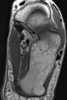

Fracture fragment

A Smith's fracture, is a fracture of the distal radius. It is caused by a direct blow to the dorsal forearm or falling onto flexed wrists, as opposed to a Colles' fracture which occurs as a result of falling onto wrists in extension. [Source: Wikipedia ]